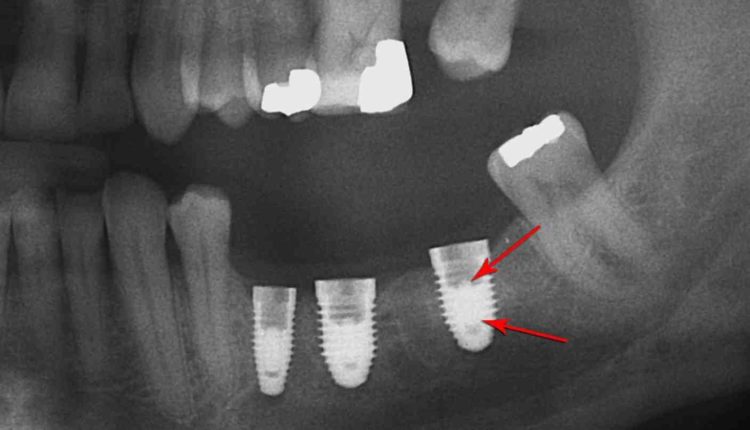

Implants can fail for a number of reasons, including lack of integration, implant fracture, implant malposition causing damage to vital structures (such as the inferior alveolar nerve, sinus membrane, a natural tooth, or an adjacent implant ) and advanced bone loss. around a loaded and integrated implant, resulting in…